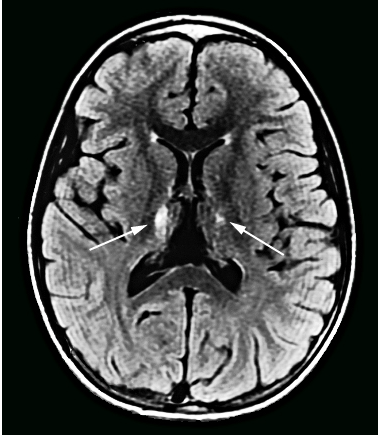

На МРТ специфическое поражение таламуса при японском энцефалите

Специфический ELISA для выявления IgM в сыворотке крови или спинномозговой жидкости может подтвердить инфекцию. Для подтверждения инфекции и дифференцировки между другими близкородственными флавивирусами (такими как вирус лихорадки денге и вирус лихорадки Западного Нила. Подробнее о поражении нервной системы при лихорадке Западного Нила читайте здесь) выполняют реакцию нейтрализации бляшкообразования. При нейровизуализации могут быть видны характерные двусторонние кровоизлияния в таламус.